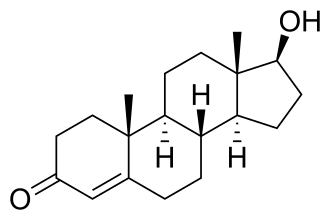

Андроге́новый реце́птор, или андроге́нный рецептор (англ. androgen receptor, AR), или NR3C4 — один из рецепторов стероидных гормонов, активируемый андрогенами — тестостероном или дигидротестостероном[1]. Относится к подсемейству 3, группе С (ген 4) семейства ядерных рецепторов, способных непосредственно взаимодействовать с ядерной ДНК[2][3]. Андрогеновый рецептор активируется при связывании с андрогенами в цитоплазме, а затем переносится в ядро.

Функции

Агонисты, антагонисты и модуляторы

Эндогенными агонистами AR являются тестостерон и дигидростерон, причём дигидростерон значительно более эффективен, чем тестостерон. Известны и синтетические агонисты AR, например, метилтриенолон[3] и производное тестостерона андриол[52]. Агонисты AR могут применяться в качестве анаболических средств[53], в андрогензамещающей терапии для лечения мужского гипогонадизма и, возможно, могут применяться в качестве мужских контрацептивов[52]. Недавние исследования показали, что связывание агонистов (как и некоторых антагонистов) может изменять последовательность ДНК, распознаваемую комплексом AR-лиганд, что может быть полезным при лечении, например, рака предстательной железы[54].